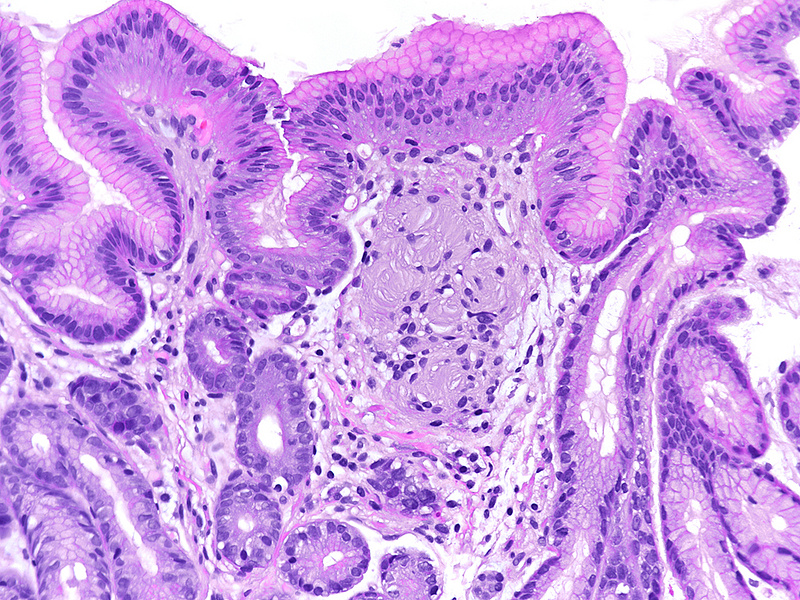

Antrum biopsy from a 52-year-old female.

Tactile corpuscle (Wagner-Meissner) – like body.

Histologically, we saw mild chronic inactive HP-negative gastritis of the antrum and corpus mucosa. Moderate atrophy and moderate predominantly complete, but also incomplete intestinal metaplasia were present in the antrum. Within the upper lamina propria an unencapsulated cluster of lamellated and concentrically arranged spindle cells with eosinophilic cytoplasm and peripherally placed nuclei was identified (Panel A). The lesion was positive for S100-protein (Panel B), prompting diagnosis of tactile corpuscle-like body or Wagner-Meissner corpuscle.